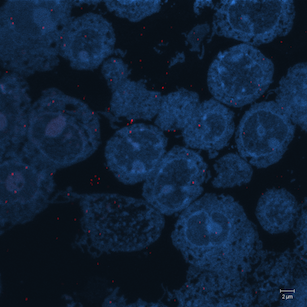

Correlative microscopy is an integration of different microscopy technologies including conventional light, confocal and electron transmission microscopy [6]. Correlative microscopic images usually involve linear or non-linear distortions which are caused by the differences between imaging systems and processing steps. Therefore, the first step of most correlative microscopy based applications is to do registration between two or more microscopic images. An example of correlative microscopic images is presented in Fig. 1.

Refer to caption

(a) Confocal Microscopic Image

(b) Resampling of Boxed Region in Confocal Image

(c) TEM Image

Figure 1: Example of Correlative Microscopy. The goal is to align (b) to (c).